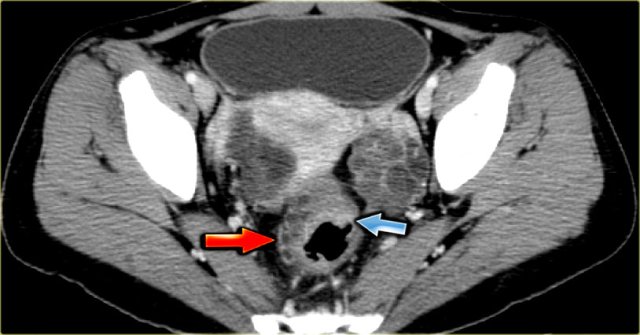

The CT image shows complex cystic masses in both ovaries.

While a serous cystadenocarcinoma may very well be bilateral, they are more often unilocular than multilocular.

Barely visible is part of a circumferential colorectal cancer (blue arrow).

Clearly visible are cystic implants on the peritoneal reflection (red arrow).

These were cystic ovarian metastases of a colorectal cancer.

This is an uncommon finding.